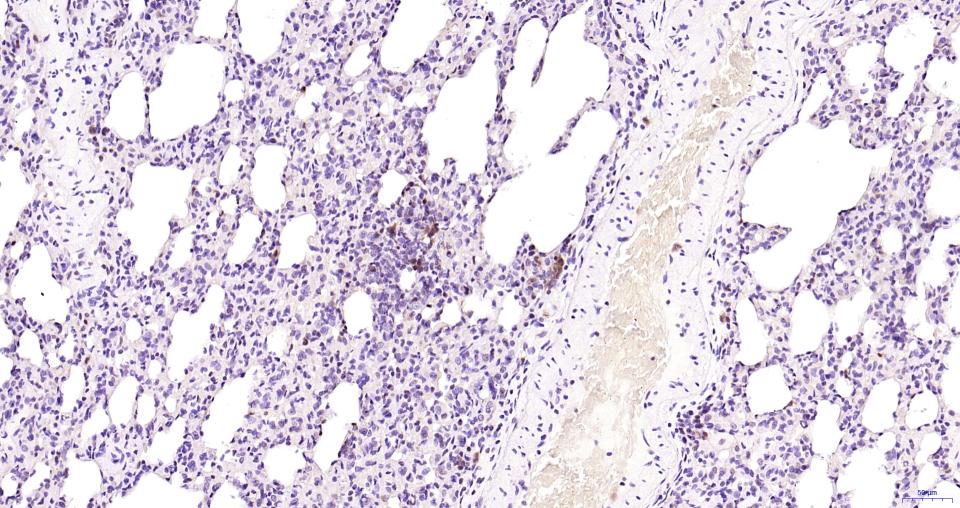

Paraformaldehyde-fixed, paraffin embedded Rat Lung; Antigen retrieval by boiling in sodium citrate buffer (pH6.0) for 15 min; Antibody incubation with Cleaved-Caspase 3 p17 Monoclonal Antibody, Unconjugated(bsm-61090R) at 1:100 overnight at 4°C, followed by conjugation to the SP Kit (Rabbit, SP-0023) and DAB (C-0010) staining.